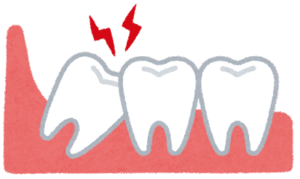

1. 激しい痛みを伴う「智歯周囲炎(ちししゅういえん)」

親知らずが斜めや横向きに生えたり、一部だけ顔を出したりすると、歯と歯茎の間に深い溝ができます。ここは歯ブラシが届かず、細菌の温床となります。 体調を崩して免疫力が落ちた時などに、この細菌が増殖して歯茎が急性炎症を起こし、激しく痛んだり、膿が出たり、顔がパンパンに腫れたりします。これが智歯周囲炎です。重症化すると口が開きにくくなったり(開口障害)、発熱することもあります。